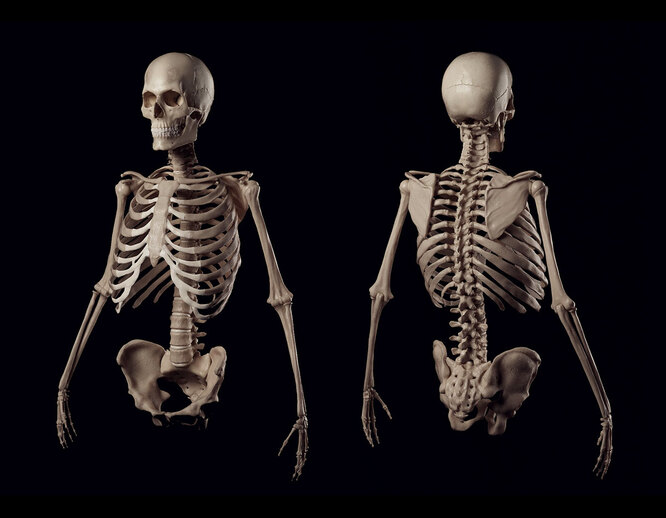

Если обратиться к базовой анатомии, то стандартное количество ребер у человека составляет 24 — это 12 пар, расположенных по обеим сторонам грудной клетки. Они формируют костную защиту для сердца, лёгких и крупных сосудов, создавая устойчивый и одновременно подвижный каркас.

Каждая дугообразная пластина состоит из двух частей — костной и хрящевой. Твёрдая основа придаёт прочность, а гибкая часть отвечает за подвижность. Первая семёрка соединена с грудиной напрямую, остальные прикрепляются косвенно или вовсе не соединяются с ней.

- Первые 7 пар — истинные. Прочно соединяются с грудиной индивидуальными хрящами, формируя жёсткий каркас.

- Следующие 3 пары — ложные. Присоединяются к грудине через общую хрящевую дугу, обеспечивая подвижность средней части грудной клетки.

- Последние 2 пары — свободные. Не соединяются с грудиной, заканчиваются в мягких тканях, легко смещаются при нагрузках.